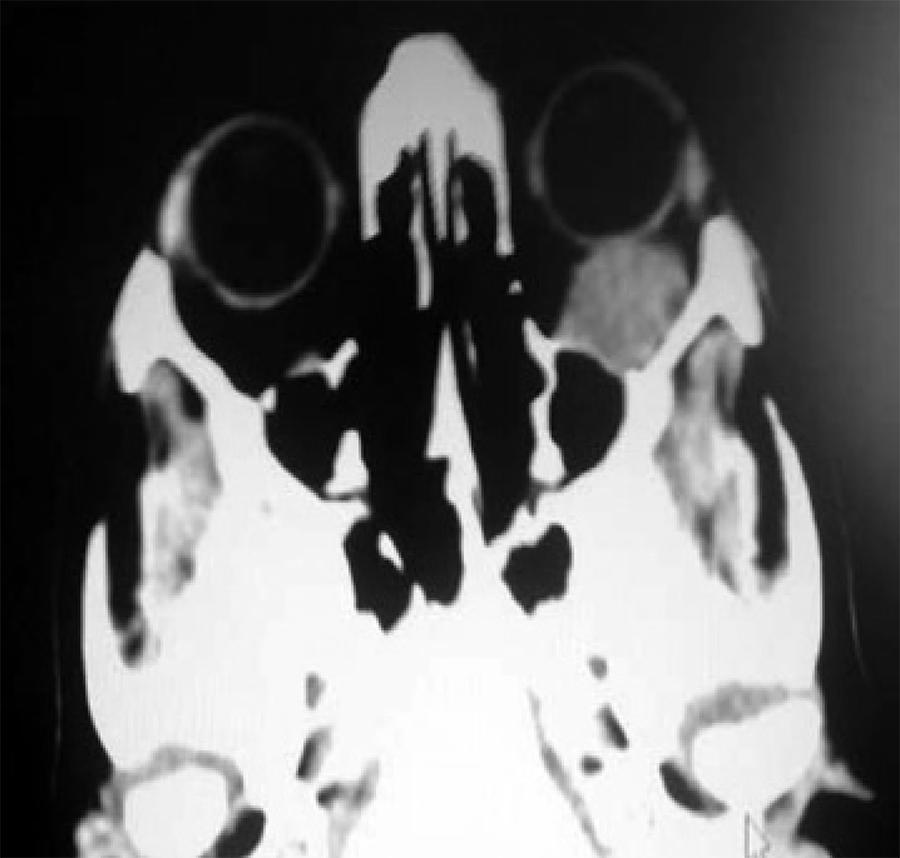

Nevertheless, given the patients' background, cerebral and orbital TC was requested, which revealed a retro-orbital mass of 15 × 25 mm compatible with orbital metastases. The mass contacted the orbit floor, without producing erosion or hyperostosis. No brain disruptions were found (Figure 4).